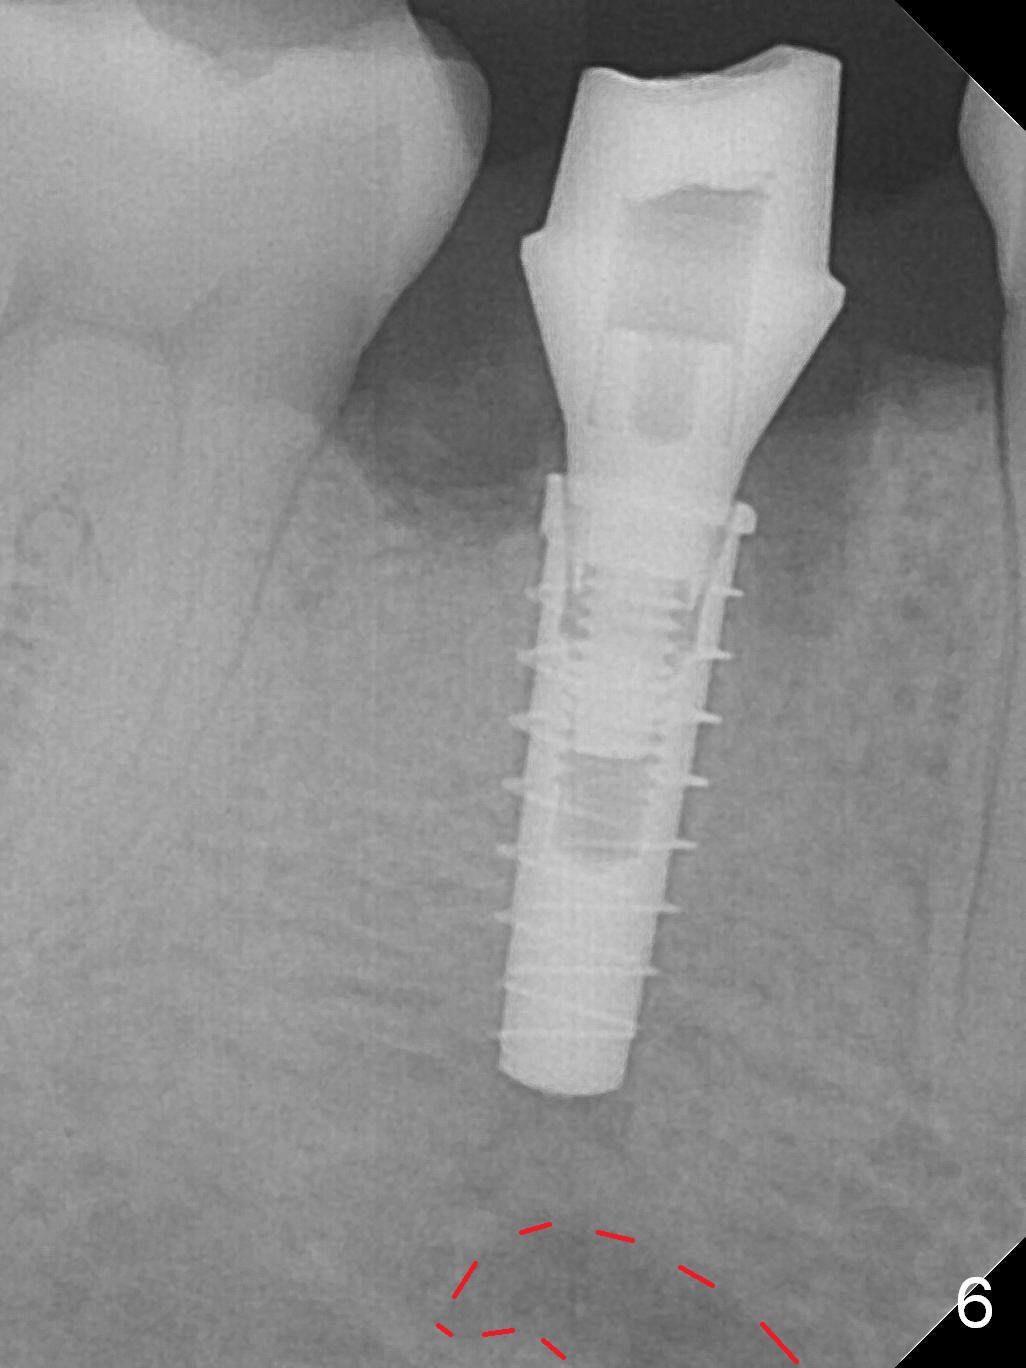

The lower 2nd primary molar has buccal furca lesion (Fig.1 *) with the thin buccal plate (Fig.2). Osteotomy is initiated in the sloped septum (Fig.3). After use of Magic Drill (MD) 3.3 mm for 13 mm and MD 3.8 mm for 11 mm, placement of a 4x11 mm IBS implant meets resistance because of the dense bone (Fig.4-6, red dashed line: Mental Loop) with final insertion torque >50 Ncm. After placement of a 6x4(3) mm abutment and autogenous bone in the remaining shallow sockets (Fig.6), a provisional is fabricated (Fig.7). Finally periodontal dressing is applied. Impression is taken 3 months postop (Fig.8). Buccal infection develops 2 weeks post cementation (Fig.9). When the crown/abutment is removed, there is no residual cement. The implant threads can be felt through the fistula. After soft tissue debridement and copious irrigation, Arestin is placed in the fistula. The latter disappears 15 days post debridement. The patient feels better and moves out of state. It appears that early periimplantitis develops because of the preexisting buccal furca lesion and failure to place the implant deep. The implant will be placed deep after loosening a little (since there is apical space (Fig.8 white line)) or removed, truncated at the apex and placed lower than the buccal crest.